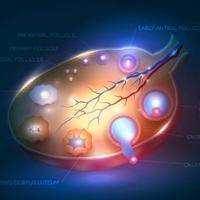

备孕是一件非常重要的事情,很多准备要孩子的夫妻都非常关心如何提高成功率。卵泡监测是备孕过程中非常常见的一种方法。但是,备孕有必要监测卵泡吗?下面我们来详细讨论一下。什么是卵泡监测卵泡监测是通过超声波或其他诊断手段,及时观察女性卵巢里的卵泡发育状况,判断卵泡大小、数量、位置、形态等指标,以便确定排卵期和最佳受孕时机。卵泡监测有哪些方法目前比较常用的卵泡监测方法有以下几种:经腹超声检查 、经阴道超声检

备孕是一件非常重要的事情,很多准备要孩子的夫妻都非常关心如何提高成功率。卵泡监测是备孕过程中非常常见的一种方法。但是,备孕有必要监测卵泡吗?下面我们来详细讨论一下。什么是卵泡监测卵泡监测是通过超声波或其他诊断手段,及时观察女性卵巢里的卵泡发育状况,判断卵泡大小、数量、位置、形态等指标,以便确定排卵期和最佳受孕时机。卵泡监测有哪些方法目前比较常用的卵泡监测方法有以下几种:经腹超声检查 、经阴道超声检

女性在平时的生活中如果不注意保养身体就很容易出现卵巢异常的情况,这种情况就会影响到女性的受孕成功率。所以有些不孕的女性会进行卵泡监测,卵泡监测可以了解清楚卵泡的生长发育。那么卵泡监测从什么时候开始?卵泡监测从什么时候开始?查卵泡配塌的时间是从月经来潮的第1天开始一直到第11天的时候。目前监测卵泡的方法主要是通过阴道彩超进行,阴道彩超的优势在于无需喝水憋尿,如果监测时没有发现优势卵泡,可间隔1到2天

卵泡监测是监测女性卵泡发育情况的的一种手段,用于确定卵子是否已经成熟,是否适合进行人工受孕或者性行为。那什么时候做卵泡监测好?测卵泡什么时候测最准大多数女性朋友为了能够顺利怀孕,都是会进行卵泡监测的,而因为对于这方面知识的欠缺,所以并不清楚自己应该在什么时候去进行卵泡监测才能得到最准确的结果,那么你知道什么时槐信候测卵泡最准吗?下面我们就来看看问题的答案吧。卵泡发育从月经第一天开始,进入卵泡期,逐

在日常生活中卵泡期是月经第几天,很多女性朋友都听说过卵泡期。卵泡期是指女性卵泡在发育成熟的时间段,也是很多女性朋友都非常关注和关心的一个事情。虽然很多人都知道卵泡期,但是对于它的具体时间是什么时候,还是有很多人不太卵泡期是月经第几天了解的,那么女性卵泡期是什么时候?女性卵泡期是什么时候?卵泡期是指从月经第3天至排卵当日。排卵就是自下次月经来潮前14天左右开始;排卵日至月经来潮为黄体期,一般为14天